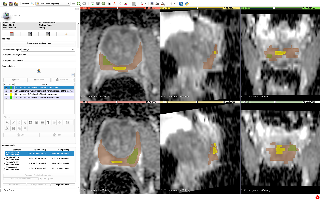

SARAS-MESAD

| 名称 | 标注内容 | 类型 | 模态 | 数量 | 标签格式 | 文件格式 | License |

|---|---|---|---|---|---|---|---|

| SARAS-MESAD | 24种动作 | 静态背景动作识别 | 内窥镜 | 4(真实手术)+5(模拟手术) | CC BY-NC-SA 4.0 |

| SARAS-ESAD | 21种手术动作 | 静态背景动作识别 | 内窥镜 | 22,601(训练)+4,574(测试) | 图片 | BB | CC BY-NC-SA |